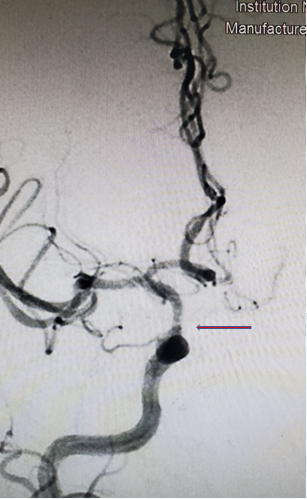

DSA:右侧颈内动脉正侧位

重要影像结论:右侧颈内动脉C6段狭窄约90%,长度约0.97cm。

术前讨论

拟行手术方案:经皮颈内动脉颅内段球囊扩张成形术、颈内动脉支架经皮植入术。